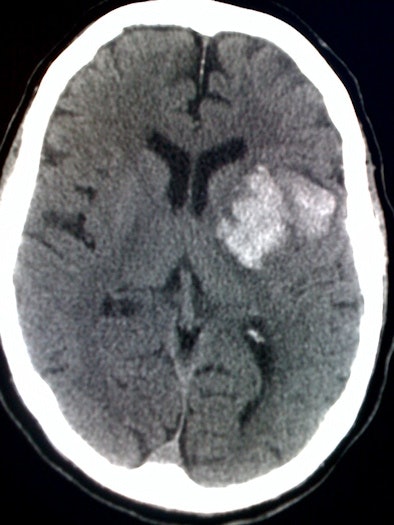

The archived images of the 88 cases in the study were displayed on a digital image monitor, and the iPhone was used to photograph one to three CT images per case. The number of photographs taken depended on the nature of the lesion.

| iPhone digital photo of head CT study. Image courtesy of Marcy Rosenberg, MD. |